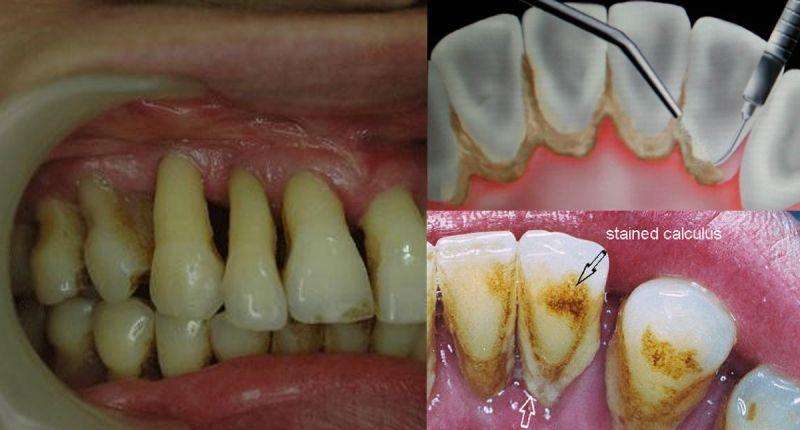

牙周病是牙周软组织因为口腔菌斑感染引起的一种慢性炎症疾病;从龈炎开始,病菌一点点的向深层感染扩散,在侵蚀掉牙周膜和牙骨质后形成牙周病。

1. 牙龈出血

牙龈炎是牙周病的一种,而出血就是牙龈炎的早期症状,所以当患者出现非剧烈外力伤害的牙龈出血、渗血时,就需要提高警惕;

不论血量是大是小,是自发性还是在刷牙等外界因素刺激下渗血,这都代表牙患者龈有炎症,处于一种不健康的状态,即使不是牙周病要尽早治疗。

1. ·初期牙周病患者通过用洁治刮治、根管治疗、拔牙、填充治疗等方式就可以控制或清除病源体,去除病因。